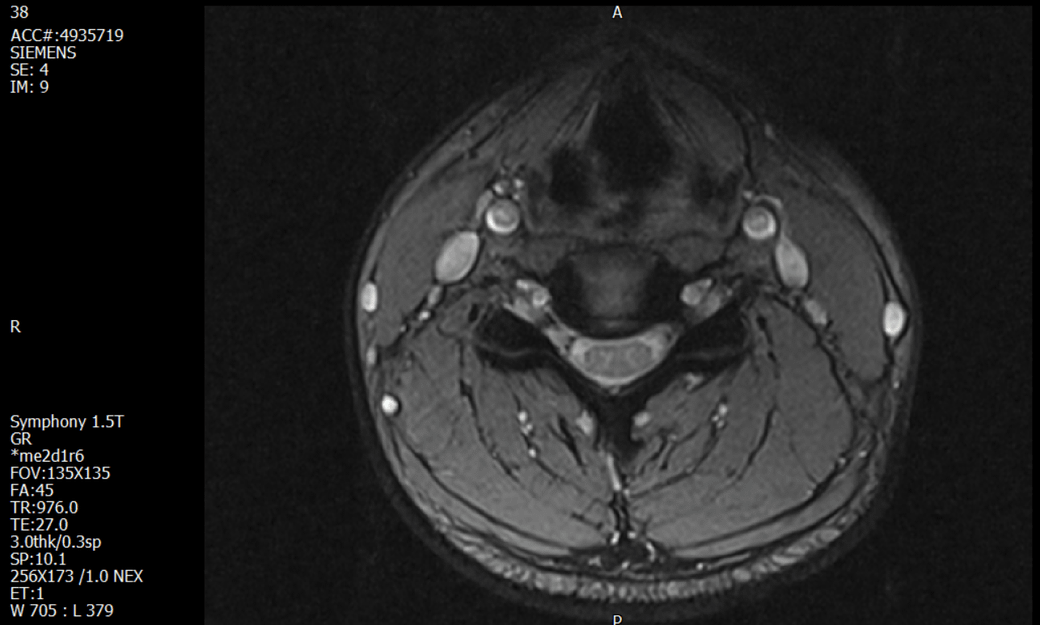

경추 요추 디스크 MRI판독 부탁드립니다.

- 3개월전 좌측 상지 저림(힘빠짐) 발생. 이틀뒤 에 좌측 하지 저림(힘빠짐) 발생.

(힘이 축처지는 느낌이라서 힘빠짐이라고 하지만, 실제 근력 문제, 감각이상, 활동 문제 없음)

1. MRI 상 , 경추와 요추에 디스크가 있나요? 있다면 좌측 팔과 다리에 저림 및 힘빠짐을 줄 정도인가요?

• 1번 째 사진

• 1. MRI 사진을 보았을 때 디스크를 의심해볼 수 있는 소견이 살짝살짝 보이긴 합니다만, 상하지의 저림 및 힘빠짐을 유발할 정도인지는 솔직히 회의적입니다.

2. 영상의 퀄리티는 나쁘지 않아 보입니다. 굳이 재촬영을 하실 필요는 없어 보입니다.

3. 개인적으로는 디스크로 인한 증상이 아닐 것으로 보나, 만약 디스크가 맞다면 우연하게 목과 허리 디스크 발병이 이틀 간격을 두고 나타났을 가능성을 생각해야 하는데, 현실적으로 그 가능성이 높지 않습니다.

4. 말씀하신 것처럼 특히 요추부 MRI는 디스크를 찾기 어렵습니다.

상기 MRI 소견으로는 심한 증상을 보일 정도는 아니며 디스크의 가능성은 적어보입니다.